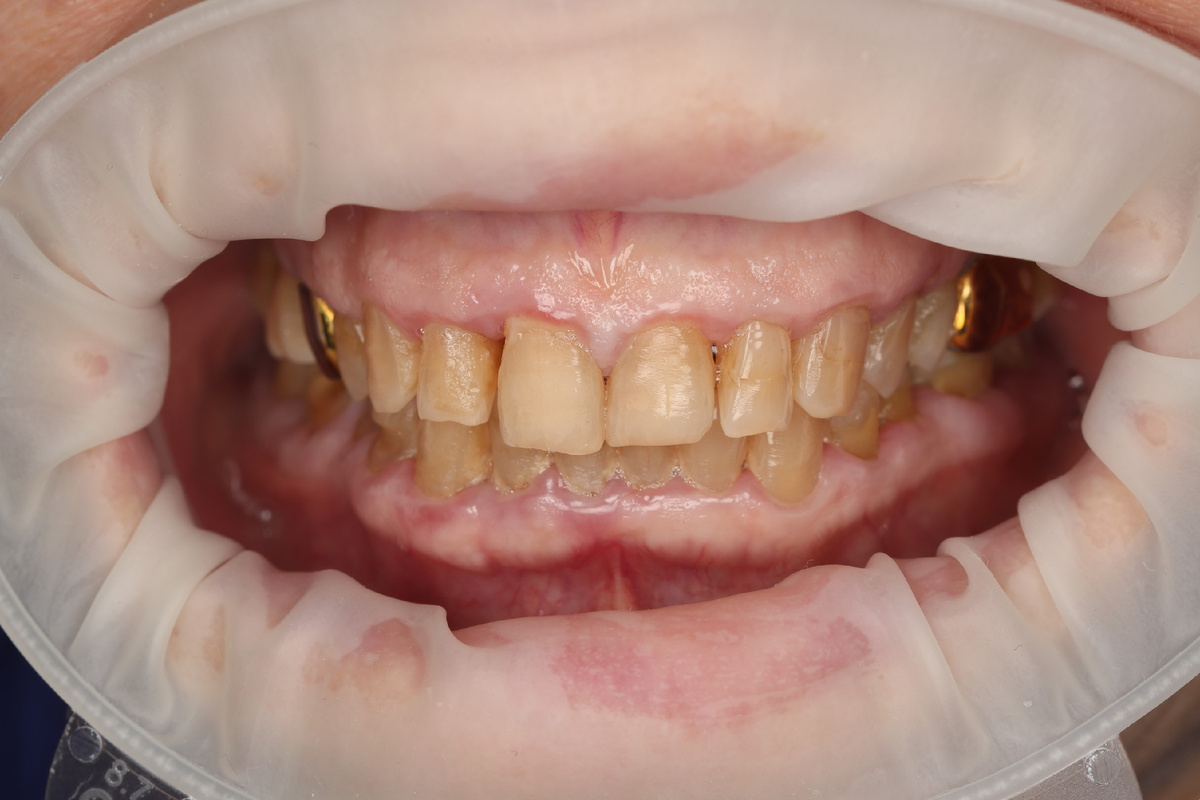

Внутриротовые фото «ДО»